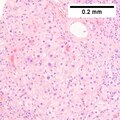

Microscopic

Requirements:[8]

• Architectural changes.

• Liver plate more than 3 cells thick - key feature.

• Loss of reticulin scaffold - incomplete loss is considered significant.

• CD34+ staining cells, suggesting loss of epithelial cells that form the sinusoids.

• Loss of structures seen in a normal liver lobule (bile ductules, portal triad).

• Invasion of the portal tract - useful in well-diff. lesions.[9]